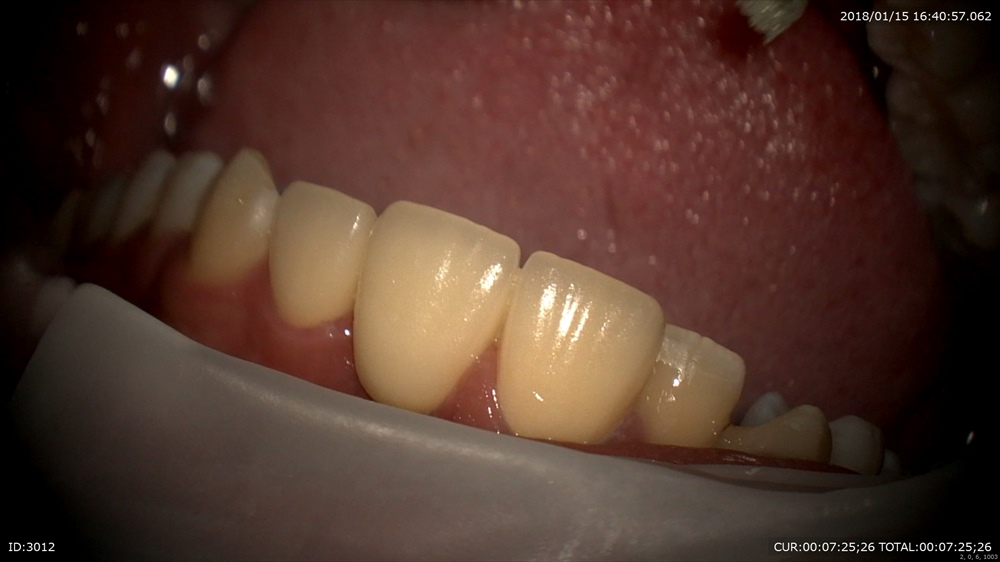

2ケース目 矯正でもどのくらい抜歯したスペースが埋まったかを患者さまが不安になられることがあります。そんな本日はこのように画像で(動画)一緒に確認!

この様にマイクロスコープは説明ツールとしても欠かせない設備になっています。八潮、埼玉。三郷、草加で詳しい治療説明ならBiVi歯科・矯正歯科まで。